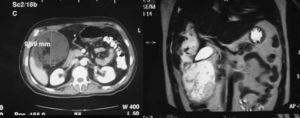

El séptimo día de estancia en UCI presenta síndrome febril, con leucocitosis en ascenso, con sospecha de abscesificación de hematoma hepático. El cuadro se resuelve con tratamiento antibiótico empírico, con disminución progresiva de las enzimas hepáticas hasta los valores normales. En la TC de control se objetiva disminución del volumen del hematoma hepático, que tiene un diámetro de 6 cm, pero se visualizan burbujas aéreas subcapsulares que indican sobreinfección de la colección; el paciente está afebril y con recuento leucocitario normal, ante lo cual se decide continuar con amplía cobertura antibiótica. En una nueva TC de control destaca un aumento del tamaño de la lesión (9,3 cm de diámetro), de contenido fundamentalmente líquido, incluyendo densidades grasas en su interior (fig. 1). Ante el aumento de tamaño de la colección hepática, se decide intervenir al paciente descartando la punción percutánea ante la posibilidad de que fuera un hematoma con sangrado activo. En el acto quirúrgico se objetiva un biloma englobado por el epiplón mayor, que desplaza el ángulo hepático del colon, dependiente del hígado (segmentos IV y V) e íntimamente adherido a la pared costal, y se procede a su drenaje quirúrgico (fig. 2) y mesohepatectomía IV–V, con hemostasia y biliestasia de la zona. La evolución fue favorable, y se dio el alta al paciente el décimo día postoperatorio.

Figura 1. A: tomografía computarizada. B: resonancia magnética. Lesión focal de margen bien definido en el parénquima hepático, con dimensiones de 9,3 × 9,8 × 24 cm, de contenido fundamentalmente líquido, alternando áreas densas con áreas hipodensas de densidad grasa.